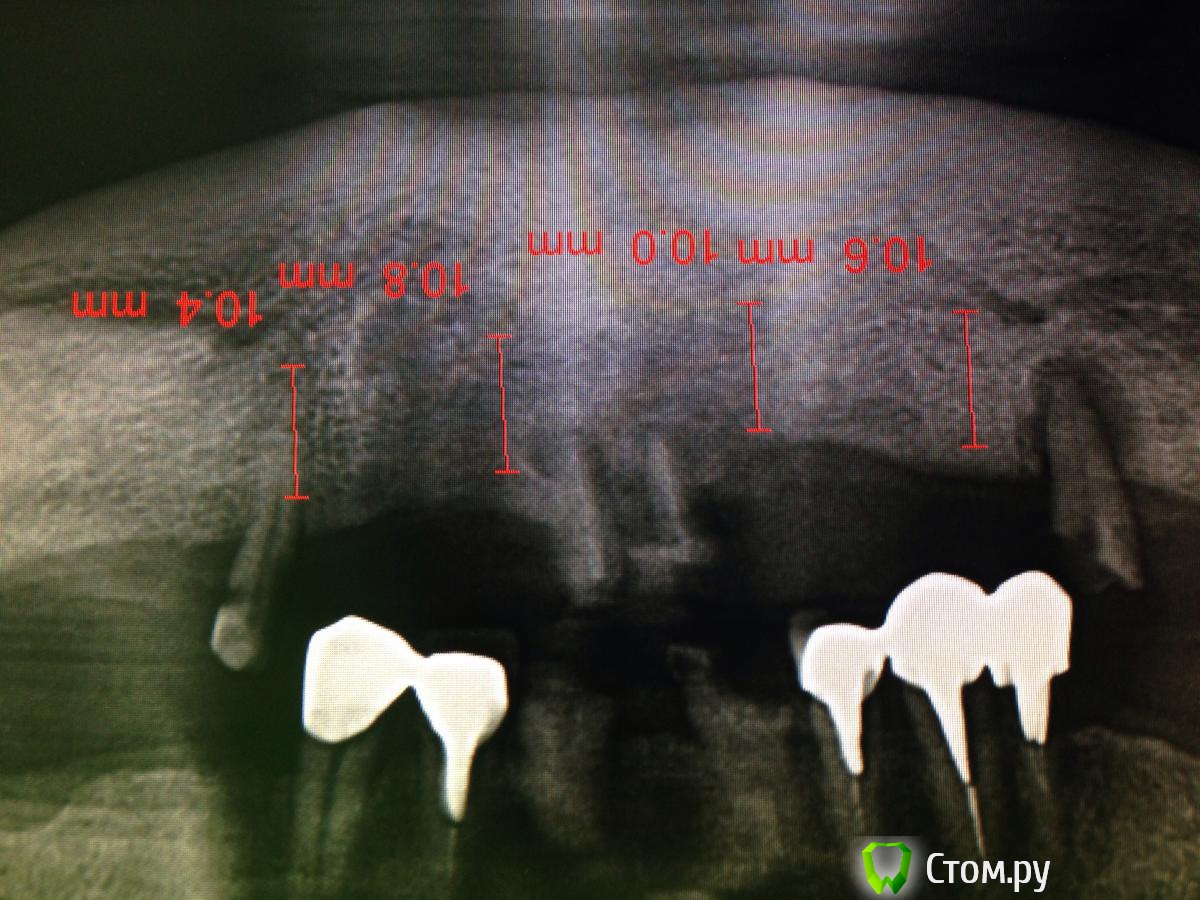

MaxDok Опубликовано 17 февраля, 2014 Поделиться Опубликовано 17 февраля, 2014 Благоприятная форма нижней челюсти для все на 4-х . А что у пациента сверху? Ссылка на комментарий

diesel87 Опубликовано 17 февраля, 2014 Автор Поделиться Опубликовано 17 февраля, 2014 еще забыл добавить, позиционирование имплантатов в уровне кости по горизонту должно быть более менее одинаковое, т.е русским языком говоря -- участок кости во фронте, лучше выравнить, но без фанатизма По поводу горизонтальной позиции и срезания не ровного гребня, что думаете по такой постановке Ссылка на комментарий

diesel87 Опубликовано 21 февраля, 2014 Автор Поделиться Опубликовано 21 февраля, 2014 В продолжение своей темы покажу что получилось 3 Ссылка на комментарий

doca Опубликовано 24 февраля, 2014 Поделиться Опубликовано 24 февраля, 2014 В продолжение своей темы покажу что получилосьPicsArt_1392992232297.jpgс таким положением имплантов -несъемнуй мост самое то 1 Ссылка на комментарий